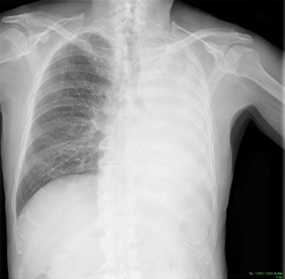

片側胸水を見たとき、どこから胸水が来ていそうか考えることが重要というのは以前のレントゲン写真で説明しました。今回は無気肺のレントゲン写真です。

無気肺では肺が白くつぶれて見えることが特徴です。横隔膜付近を確認すると辺縁が追える場合は無気肺であることが多いです。胸水の場合は辺縁が追えないくらい真っ白になります。

このレントゲン写真では、左無気肺であることが分かります。

別の見極め方としては、気管が病変と同側に偏位しているならば無気肺であり、気管が病変と対側に押しやられているなら腫瘤や胸水を想定する方法もあります。

本症例は同側に偏位しています。そこからも無気肺が想定されます。